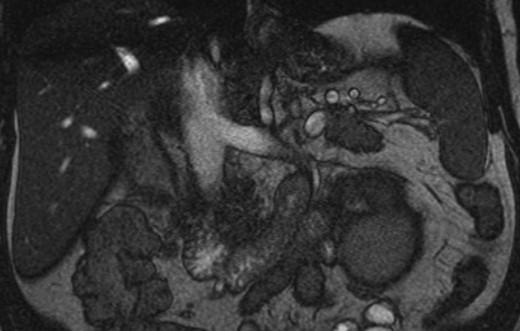

A 51-year-old white male with BMI of 29.7 was referred for gross hematuria. Renal ultrasound identified right hydronephrosis and ureteroscopy demonstrated high grade T2 urothelial carcinoma. CT and MR imaging revealed an 8 cm upper pole infiltrative tumor which obliterated the right renal vein without caval thrombus (Figs 1 and 2). There was no evidence of metastasis on CT chest. The preoperative estimated glomerular filtration rate was 71 ml/min/1.73 m2. Multidisciplinary review was undertaken and a radical nephroureterectomy and lymph node excision was recommended without neoadjuvant chemotherapy.

Coronal MRI of the abdomen/pelvis demonstrating no evidence of caval thrombus. The right renal vein was not visible on MRI.